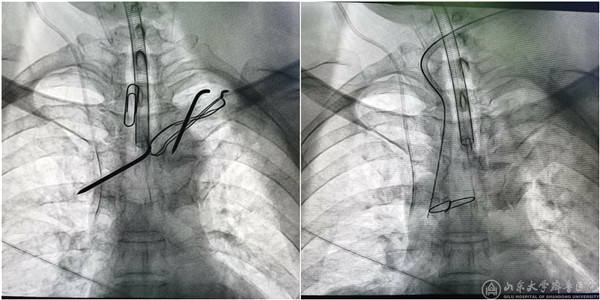

8月26日下午,在第一手术室的杂交手术间,杨长勇教授作为主刀医生、桑锡光教授作为助手,经多学科联合协作,成功将嵌于患者纵膈内的钢针取出。术中见钢针横卧在无名静脉前面,被血管被膜增生组织包绕,几次分离都面临大出血的风险,最终顺利取出钢针。目前,患者术后恢复良好并顺利出院。

(钢针取出前后钢针透视)